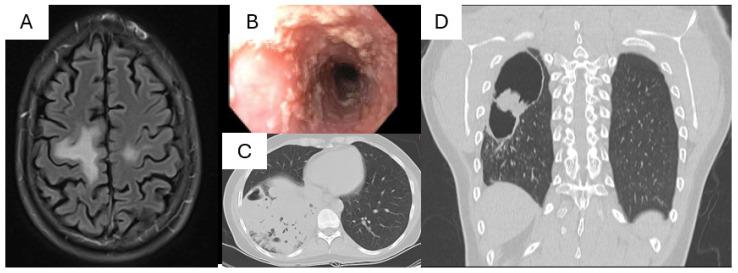

The Janus kinase (JAK)-signal transducer and activator of transcription (STAT) pathway is highly conserved and essential for numerous biological functions triggered by extracellular signals, including cell proliferation, metabolism, immune response, and inflammation. Defects in STATs, either loss-of-function or gain-of-function defects, lead to a broad spectrum of clinical phenotypes in humans, including a wide range of infectious complications. The susceptibility to pathogens can stem from defects in immune cells within the hematopoietic compartment, impaired barrier functions of non-hematopoietic compartment, or a combination of both, depending on the specific STAT defect as well as the pathogen exposure history. Effective management involves antimicrobial prophylaxis tailored to the patient's infection risk and improving disease control with targeted therapies and/or hematopoietic cell transplantation.